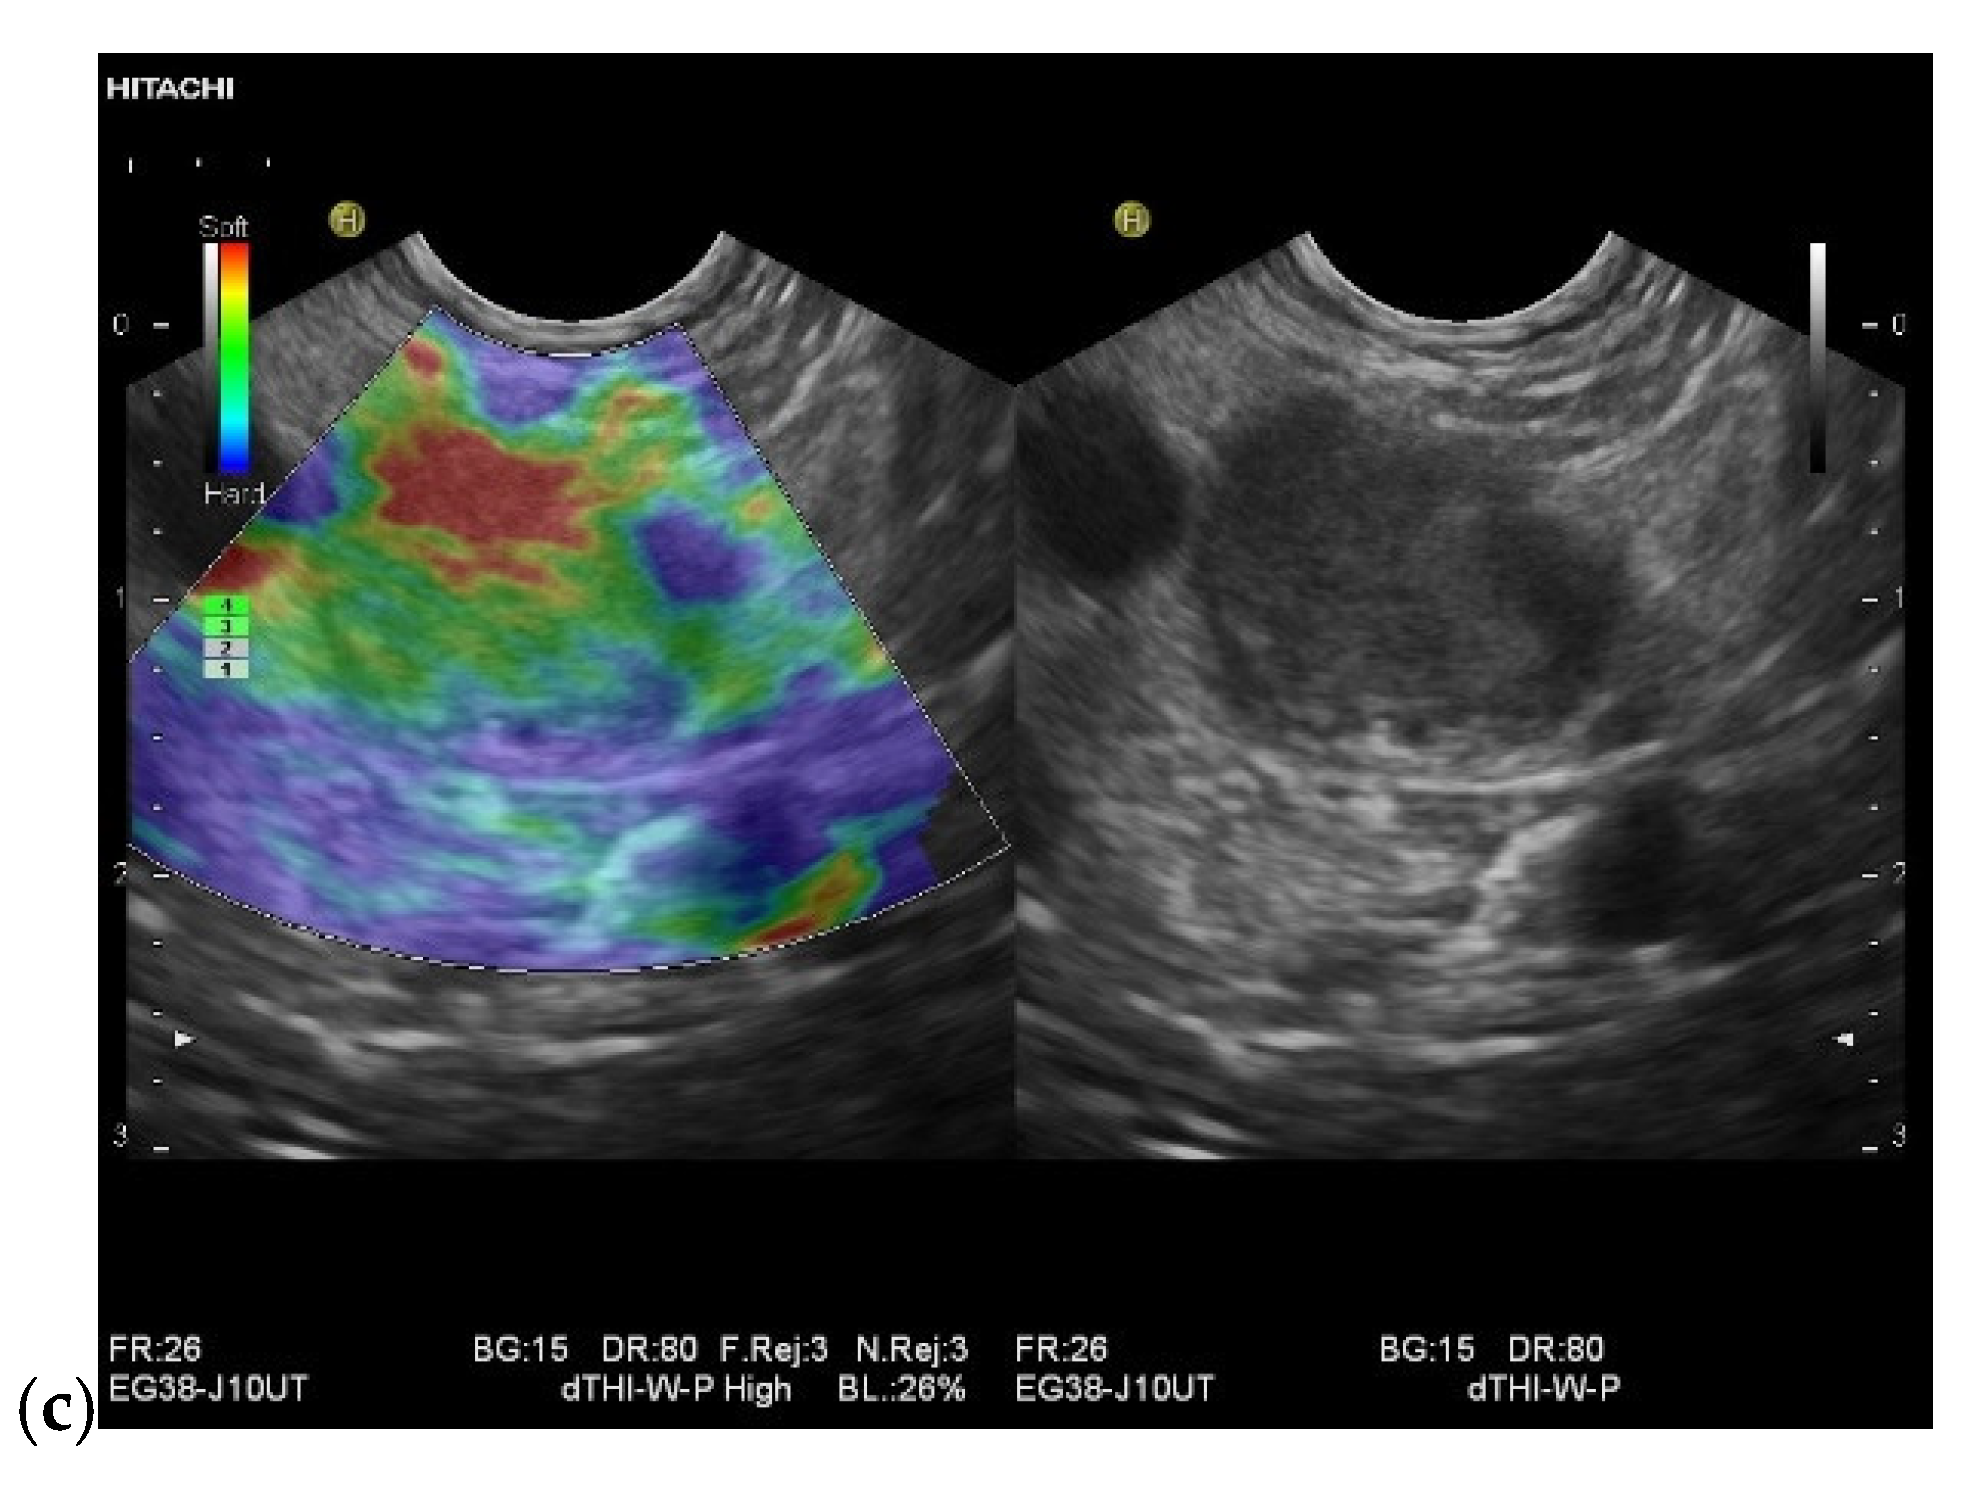

| Elastography (small lesions up to 15 mm) [67] | 41% softer or isoelastic, 59% stiffer compared to pancreatic parenchyma | 4% soft or isoelastic, 96% stiffer compared to pancreatic parenchyma | 64% soft or isoelastic, 36% stiffer compared to pancreatic parenchyma |

- Ignee, A.; Jenssen, C.; Arcidiacono, P.G.; Hocke, M.; Moller, K.; Saftoiu, A.; Will, U.; Fusaroli, P.; Iglesias-Garcia, J.; Ponnudurai, R.; et al. Endoscopic ultrasound elastography of small solid pancreatic lesions: A multicenter study. Endoscopy 2018, 50, 1071–1079. [Google Scholar] [CrossRef]